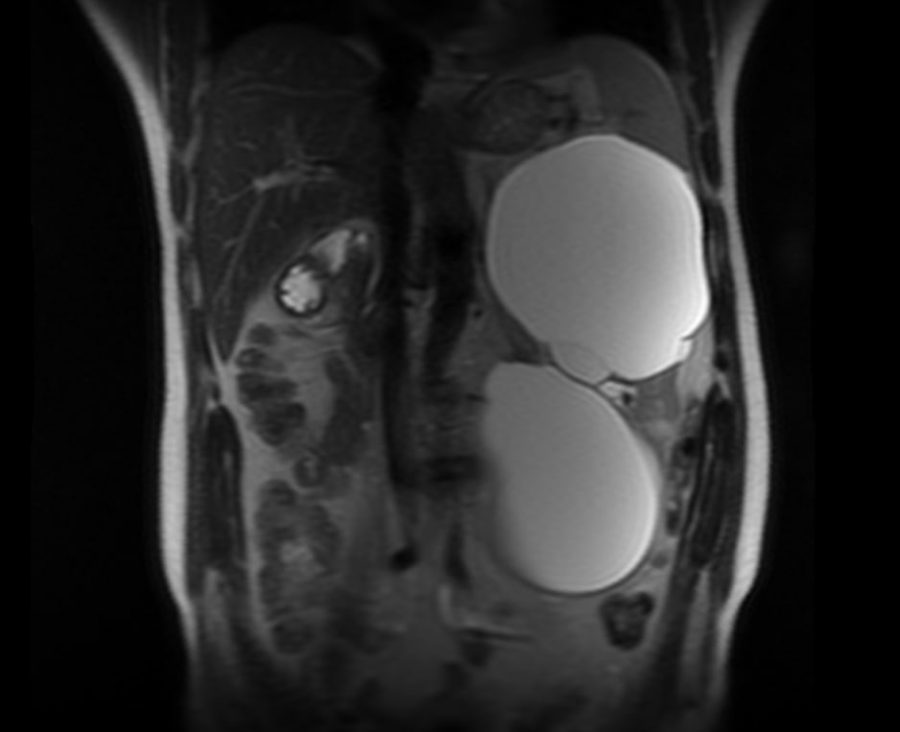

Пациент 49 лет прооперирован в отделении урологии БУЗ Орловской области «ООКБ» по поводу гигантских кист левой почки.

—  Случай является интересным в  связи тем, что объем двух кист составил около 4  литров, а  почка занимала всю левую часть брюшной полости до  малого таза,  — отмечают в  группе ВКонтакте медучреждения.

Сообщается, что операция была выполнена лапароскопическим доступом  — через три маленьких прокола. Благодаря применению современных малоинвазивных технологий пациенту не  требуется долго пребывание в  условиях стационара после операции.

Пациент был выписан на  амбулаторное наблюдение по  месту жительства.